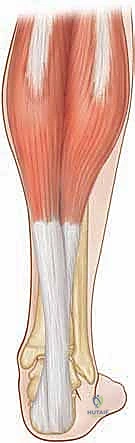

مجموعة عضلات الساق ثلاثية الرؤوس (Triceps Surae)

تُعد هذه المجموعة العضلية المحرك الأساسي لعملية الدفع أثناء المشي (الانثناء الأخمصي للقدم). تتكون من عضلتين رئيسيتين تندمجان لتكوين وتر أخيل:

العضلة التوأمية الساقية (Gastrocnemius Muscle):

هي العضلة السطحية ذات البطنين (رأس إنسي ورأس وحشي). تنشأ هذه العضلة من الجانب الخلفي للقمة الإنسية والوحشية لعظم الفخذ البعيد (فوق مفصل الركبة). تتحول أليافها العضلية الكثيفة إلى ألياف وترية مسطحة في منتصف الساق، لتشكل المكون السطحي والخلفي لوتر أخيل.

نقطة سريرية هامة: نظراً لأن العضلة التوأمية تنشأ من الفخذ، فهي تُعد "عضلة ذات مفصلين" (تؤثر على حركة الركبة والكاحل معاً). هذه الخاصية التشريحية هي الأساس لـ "اختبار سيلفرفسكولد" (Silfverskiöld Test)، الذي يعتمد عليه الدكتور هطيف بدقة للتمييز بين قصر العضلة التوأمية المعزول، وبين قصر مجمع العضلات بأكمله. -